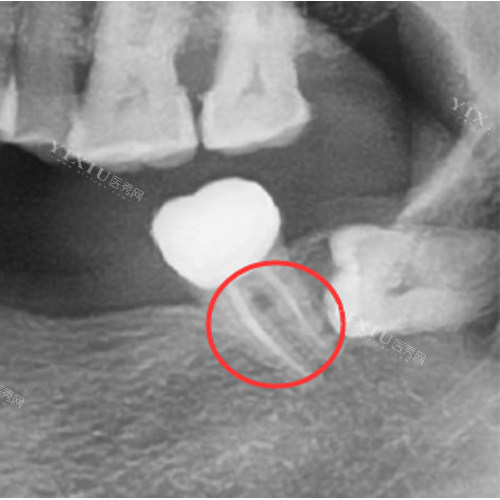

3. 折裂的“发展路径”:从隐裂到完全断裂

隐裂:牙面出现细微裂纹,冷热刺激敏感

牙冠折裂:部分牙体崩落,可能暴露根管

纵裂:牙齿沿根管方向完全断裂,需拔除

根管治疗后的牙齿